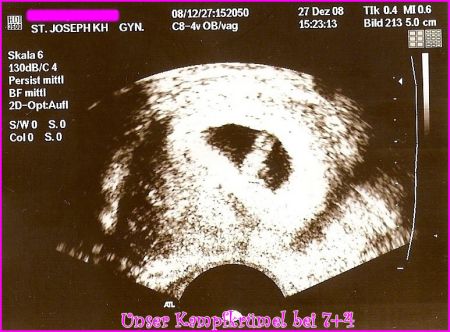

Unser Kampfkruemel alias Erdnuss in der 8. Schwangerschaftswoche!